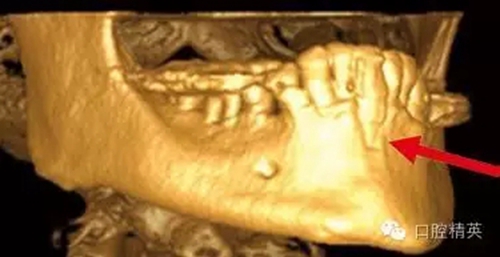

圖3a:術(shù)后的三維影像重建給外科醫(yī)生對(duì)手術(shù)入路的回顧以提示。對(duì)于這一病例進(jìn)行了Caldwell-Luc術(shù)式,用球鉆在上頜竇側(cè)壁做一窗口,直接入路取出種植體。

我們通過文獻(xiàn)和網(wǎng)站檢索獲得了一些關(guān)于種植體失敗的研究和綜述文章。一個(gè)和僅使用兩維放射診斷(根尖片或曲斷片)有關(guān)的常見失敗是上頜竇穿孔。(圖1a-c)通常牙醫(yī)由于錯(cuò)誤的估計(jì)了上頜竇底骨量高度而造成幾個(gè)毫米的上頜竇底穿孔。一些病例可能沒有癥狀,象圖中所示的這個(gè)病例,患者需要嚴(yán)格的監(jiān)控、復(fù)查。有些病例則出現(xiàn)并發(fā)癥,種植體不得不取出。

另一個(gè)和醫(yī)生僅用兩維放射線檢查造成的特殊并發(fā)癥是種植體進(jìn)入上頜竇。(圖2a-c)可能成為上頜竇異物的有牙齒,牙根,印模材料,牙科器械,近年來又增加了一個(gè)—種植體??上攵瑥纳项M竇中取出異物對(duì)患者來講是創(chuàng)傷很大的。

其他研究也報(bào)道過,對(duì)于這種病例,唯一的選擇是用根管顯微鏡或Caldwell Luc技術(shù)從上頜竇中取出種植體。有些文章報(bào)道了如何處理進(jìn)入上頜竇的種植體,但很少?gòu)念A(yù)防的角度來談這個(gè)問題,其實(shí)很簡(jiǎn)單,術(shù)前應(yīng)該應(yīng)用CBCT成像檢查。